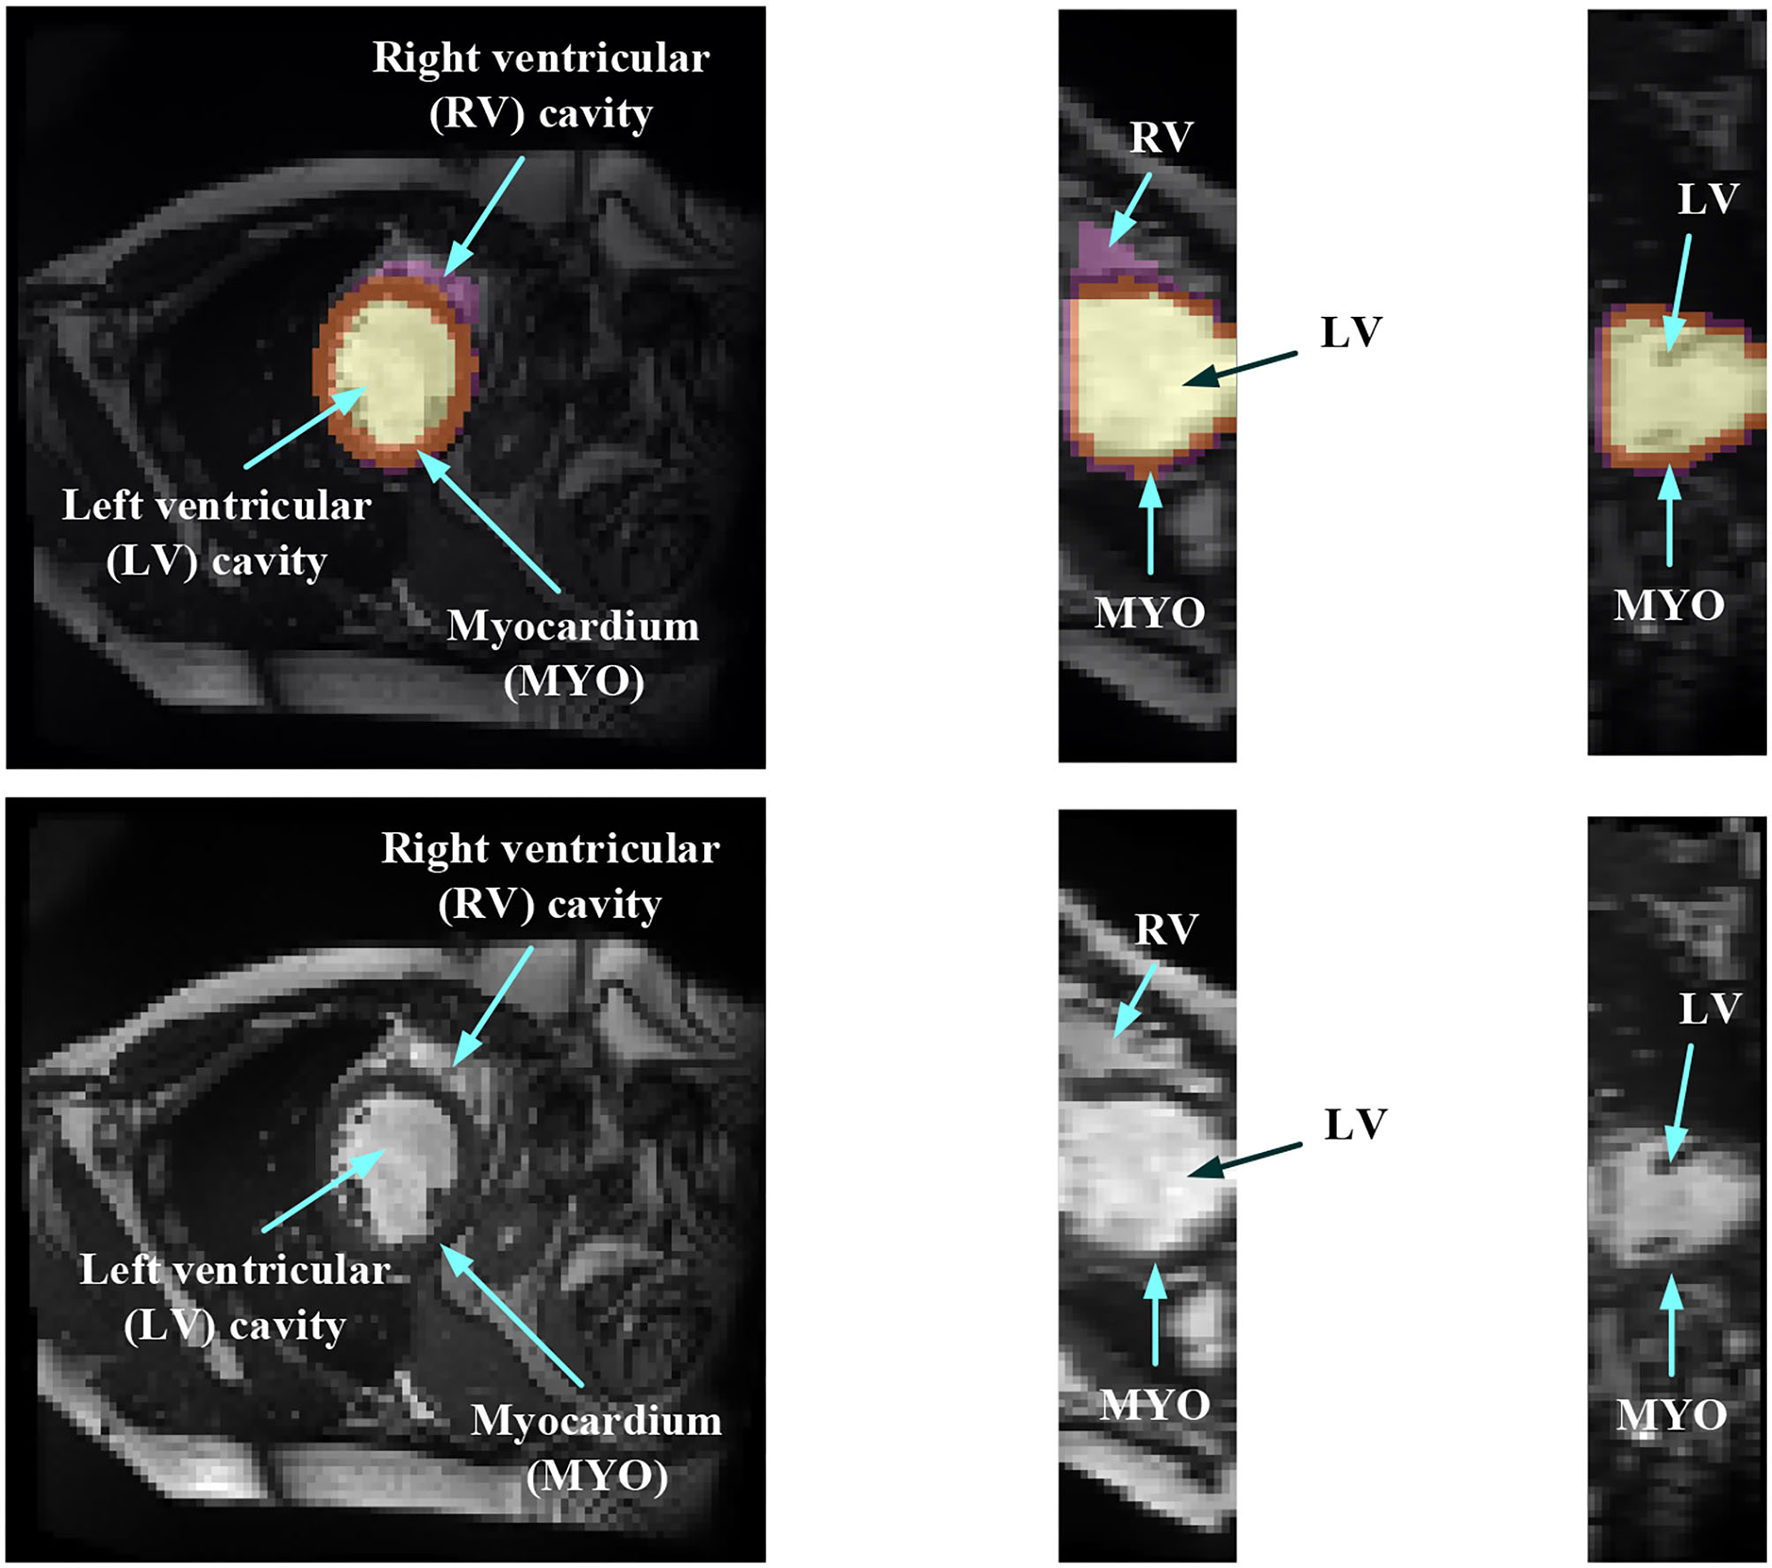

In order to evaluate the MYO function, accurate segmentation of the LV cavity, RV cavity, and MYO need to be acquired from the framework. Figure 1 shows the slices of typical CMR images of a patient at ED frame with and without ground truth mask along each axis, respectively. The label shows the ground truth of segment results for different parts of the CMR image.

Figure 1

Structure illustration of a typical CMR image. The images are the slices on the z-axis, y-axis, and x-axis, respectively, from Patient 001 in the automated cardiac diagnosis challenge (ACDC) dataset at end-diastolic (ED) frame with mask, and the second row of the figure is the raw CMR slices of Patient 001.

Medical image segmentation has attracted much attention recently (19–26). MYO segmentation of CMR sequences has the following challenges. First, the contrast between the myocardium and surrounding structures is low as shown in Figure 1. Second, the brightness heterogeneity in the left and RV cavities is due to blood flow (3). Third, misleading structures such as papillary muscle have the same intensity and grayscale information as myocardium, which makes it hard to extract the accurate boundary. There are two approaches among existing works toward myocardium segmentation.